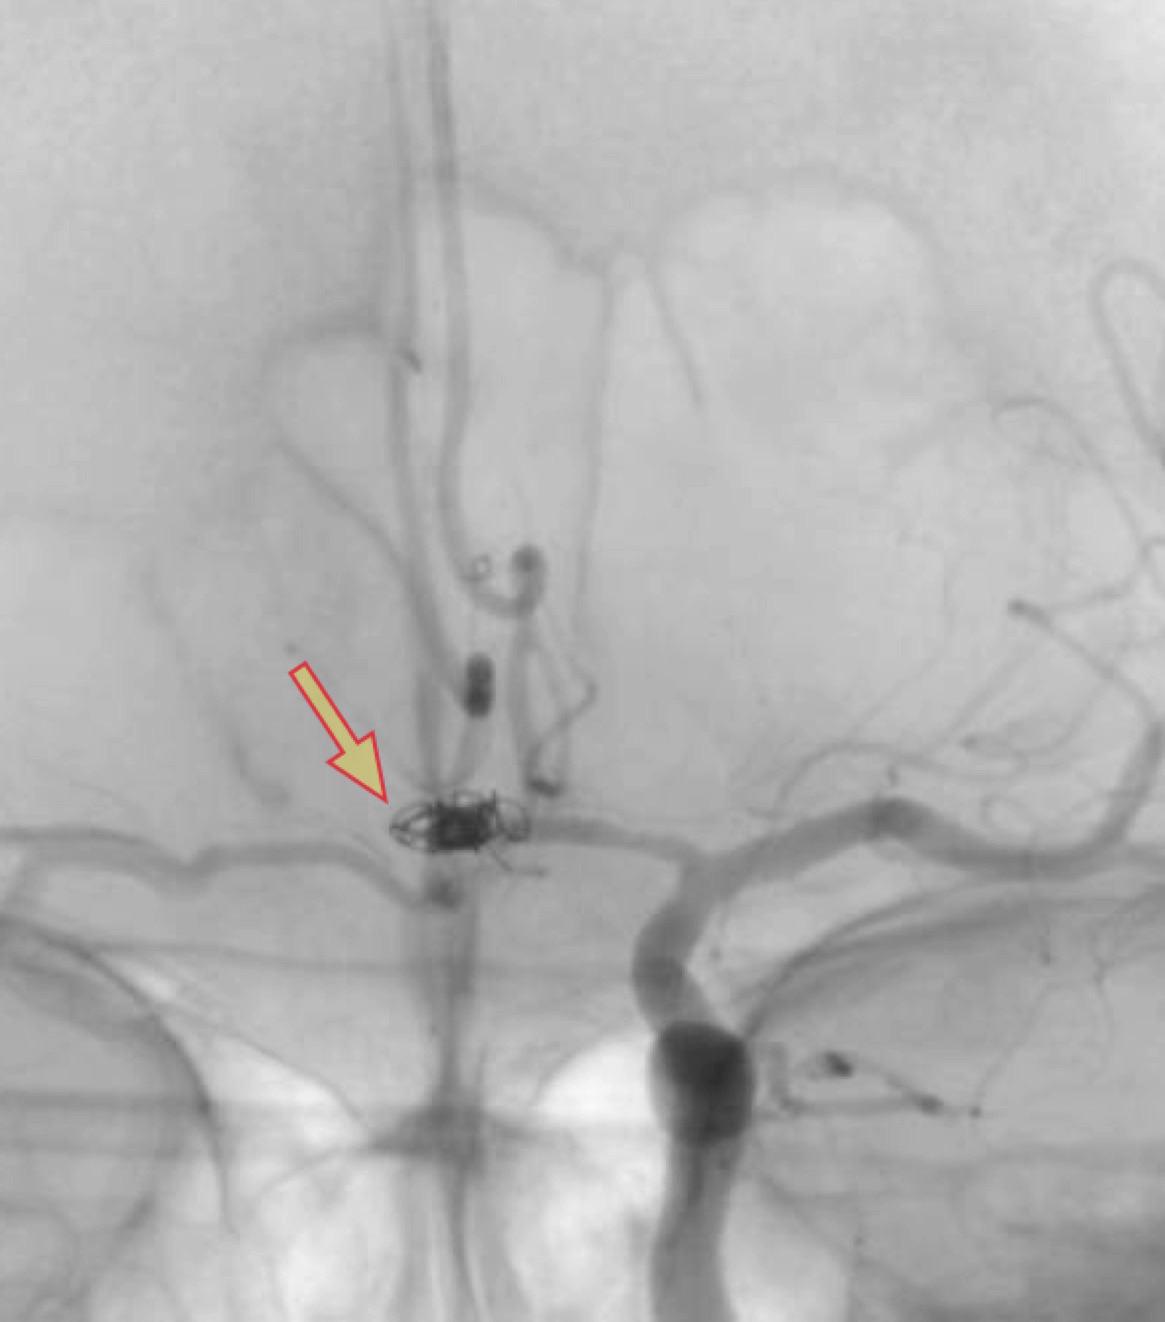

特に即効性があるのはバルーンによる治療(PTA)です。以下に、私の経験した症例を提示いたします。

遅発性脳血管攣縮に対するPTA治療

<治療前>矢印の部分が狭窄部

<治療後>矢印の部分が治療後に拡張した部分